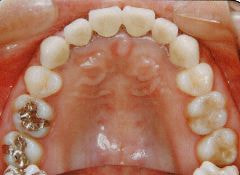

治療例1 (インプラント補綴+矯正)